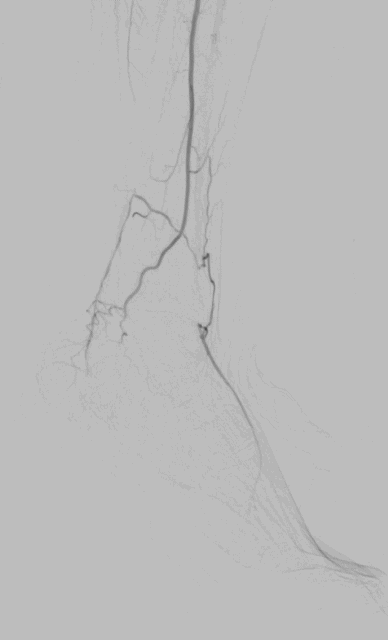

手术过程(二):股动脉入路,翻山左下肢动脉造影

图片

支架植入前造影